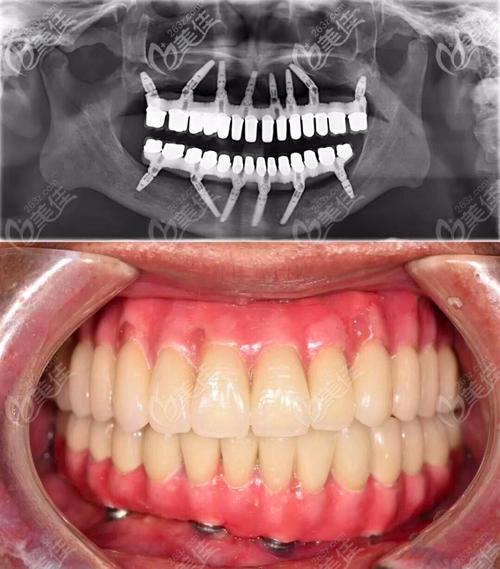

看,上海雅悦齿科刘定斌院长穿颧穿翼全口种植牙价格和

全口种植牙图片